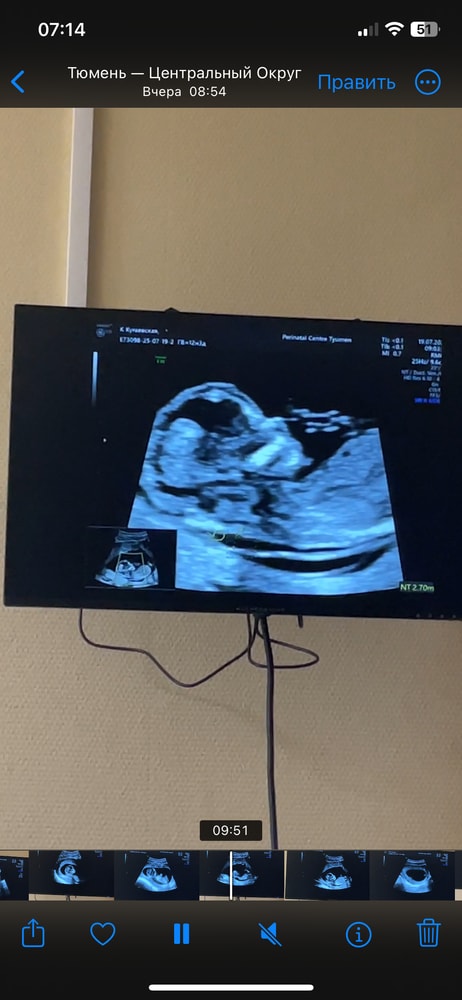

на 1 скрининге на сроке 12.4 недели

ктр 7,1см

Твп 2,8мм

срок по узи 13,2 недели.

все остальные показатели в норме. На узи напугали про твп чуть выше нормы.

Все измерения на фото скринах с узи. Не нашла вообще 2.8

Abigeil, просто странно, три раза намеряла 2,4. Потом один раз 2,7. В итоге написали 2,8